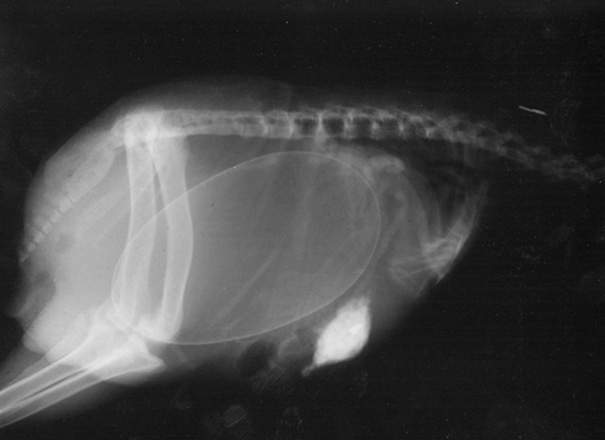

▼懷孕的奇異鳥(肚子裡不是奇異果喔w)

圖片來自:boredpanda